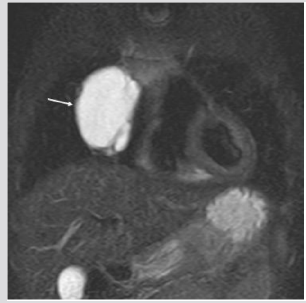

Figure 7: Five months old female. MRI, (T2w sequence). Hyperintense septated paracardiac mass. At surgery: macrocystic lymphatic malformation.